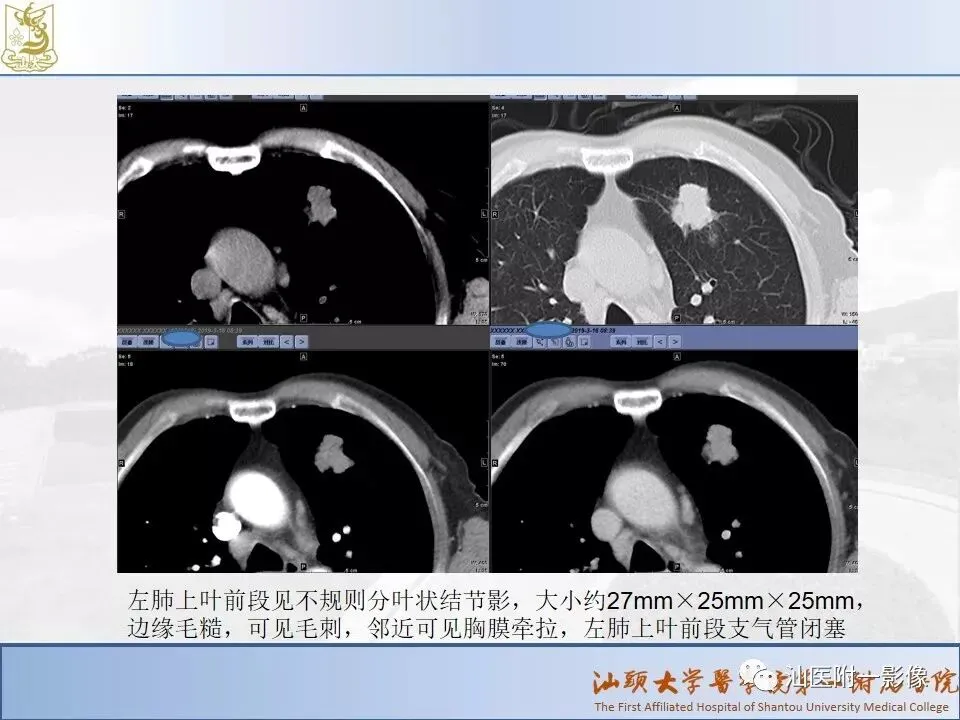

肺结节分类、处理及浅识肺结节分类影像报告和数据系统(Lung-RADS)

来源:汕医附一影像

说明:本课程病例主要来源于本院病例及参考资料,

无涉及病人隐私,仅做教学用途。